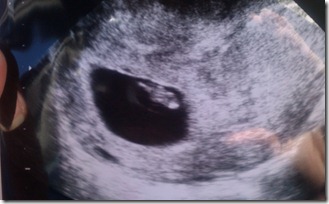

When we went in 3 weeks ago, Dr.Cline wanted me to be cautious. The baby had not completely attached to the placenta, and normally by this point they have. He didn’t seem alarmed, but did want to stop exercising, go completely off of pop and a few other precautions just be safe!

This morning I went in for our second sonogram, to make sure that everything look good!

EVERYTHING LOOKED GREAT!

I was able to see the baby moving his/her arms, and I was able to see the umbilical cord COMPLETELY ATTACHED! I have always been in awe at the creation of life, and how carefully our Lord weaves these babies together, but it becomes so much more real when I see such a difference in just 3 weeks!!